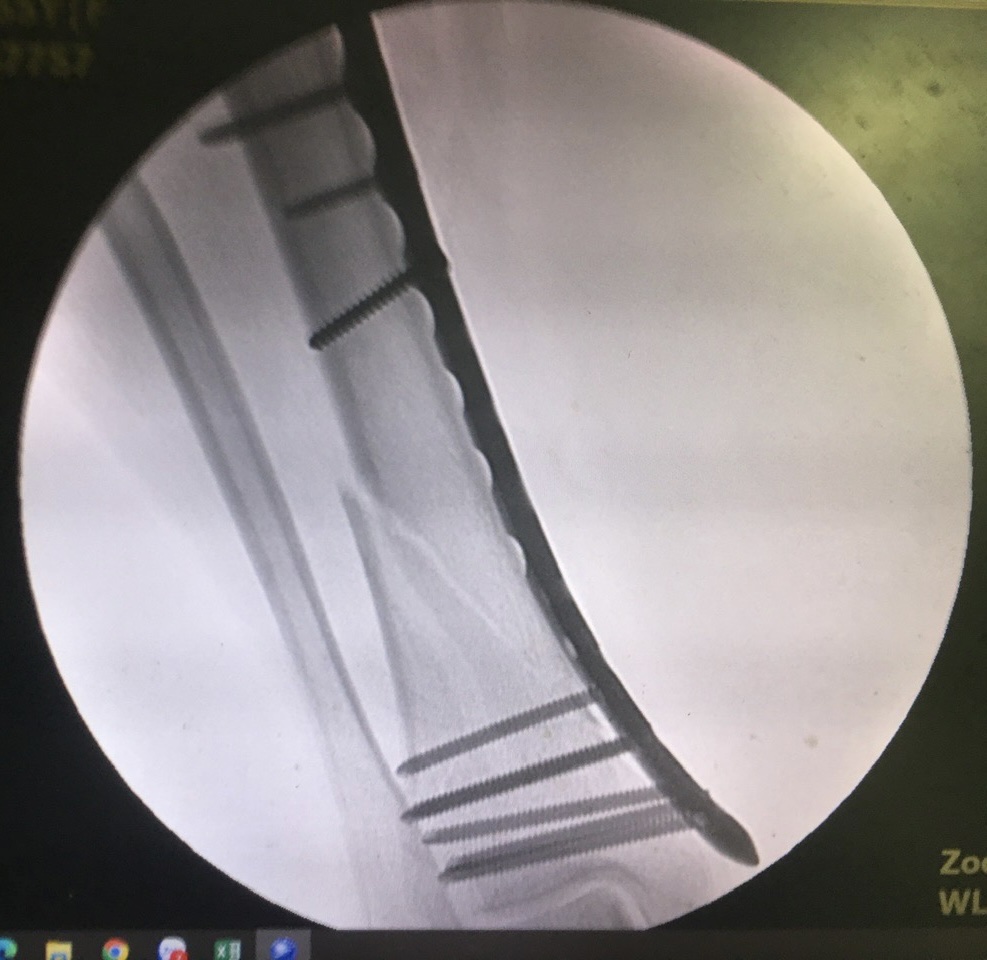

Hình ảnh chụp ở máy C-Arm tại phòng mổ lúc phẫu thuật kết hợp xương “Xâm lấn tối thiểu" cho bệnh nhân.

Nhiều năm qua, Khoa Ngoại chấn thương, Bệnh viện Đa khoa Trung ương Quảng Nam đã phẫu thuật thành công cho nhiều trường hợp gãy xương bằng phương pháp MIPO. Mới đây nhất là người bệnh Võ Văn D. (62 tuổi, trú huyện Bình Sơn, tỉnh Quảng Ngãi) bị Đa chấn thương do TN Giao thông, gãy 2 mâm chày phức tạp Schatzker V, bệnh nhân được phẫu thuật kết hợp xương bằng nẹp khóa theo phương pháp MIPO với thời gian phẫu thuật chỉ 45 phút; kết quả sau mổ xương gãy được nắn chỉnh hoàn hảo, và xuất viện sau 5 ngày.

Trước và sau phẫu thuật theo phương pháp MIPO cho người bệnh Võ Văn D. (62 tuổi, trú huyện Bình Sơn, tỉnh Quảng Ngãi).